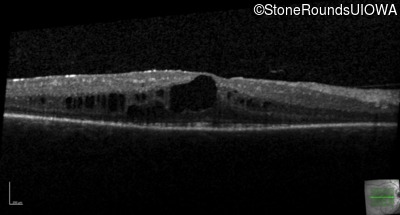

Optical Coherence Tomography - Right - 20/30 -2

Exemplar / OCT Stack